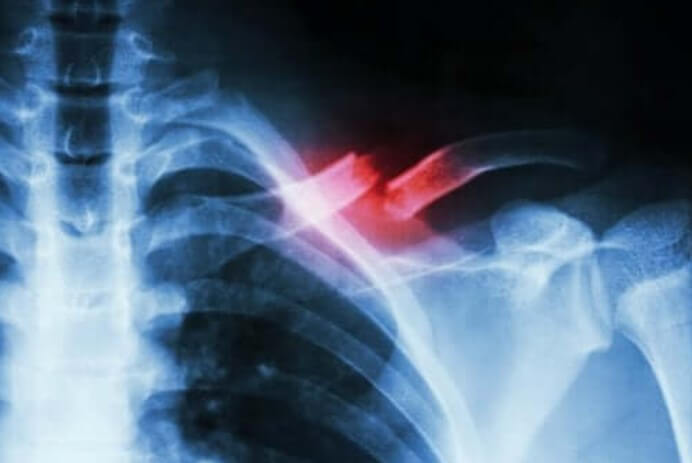

Αυτοί οι τύποι καταγμάτων δεν είναι εύκολο να διαγνωστούν. Επομένως, απαιτούν ιατρικό προσωπικό που είναι ειδικευμένο και συμπληρωματικές εξετάσεις για να το διακρίνουν από άλλες καταστάσεις. Αυτό συμβαίνει επειδή το κάταγμα δεν ανιχνεύεται συνήθως σε μια ακτινογραφία.

Το κάταγμα εκ κοπώσεως είναι ένα είδος σχισμής ή ρωγμής στο οστό. Συμβαίνουν λόγω επαναλαμβανόμενου μικροτραύματος ή υπερφόρτωσης, όπως είπαμε παραπάνω. Επιπλέον, μπορεί να παρουσιάσουν σοβαρό πόνο κατά την εκτέλεση ορισμένων σωματικών δραστηριοτήτων. Στη συνέχεια, εξαφανίζονται όταν τελειώνουν οι δραστηριότητες.